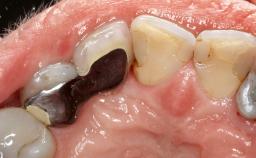

In this case, Mario Roccuzzo utilizes surgical bone regeneration treatment around implant 46 using a bone graft substitute and a connective tissue graft to resolve peri-implant inflammation, reduce the probing depths, and prevent further progression of disease.

A 58-year-old-male patient was referred in February 2007 for implant placement in the right mandibular molar area. Two tissue level implants were inserted at sites 44 and 46, respectively, to support a three-unit fixed dental prosthesis (FDP).